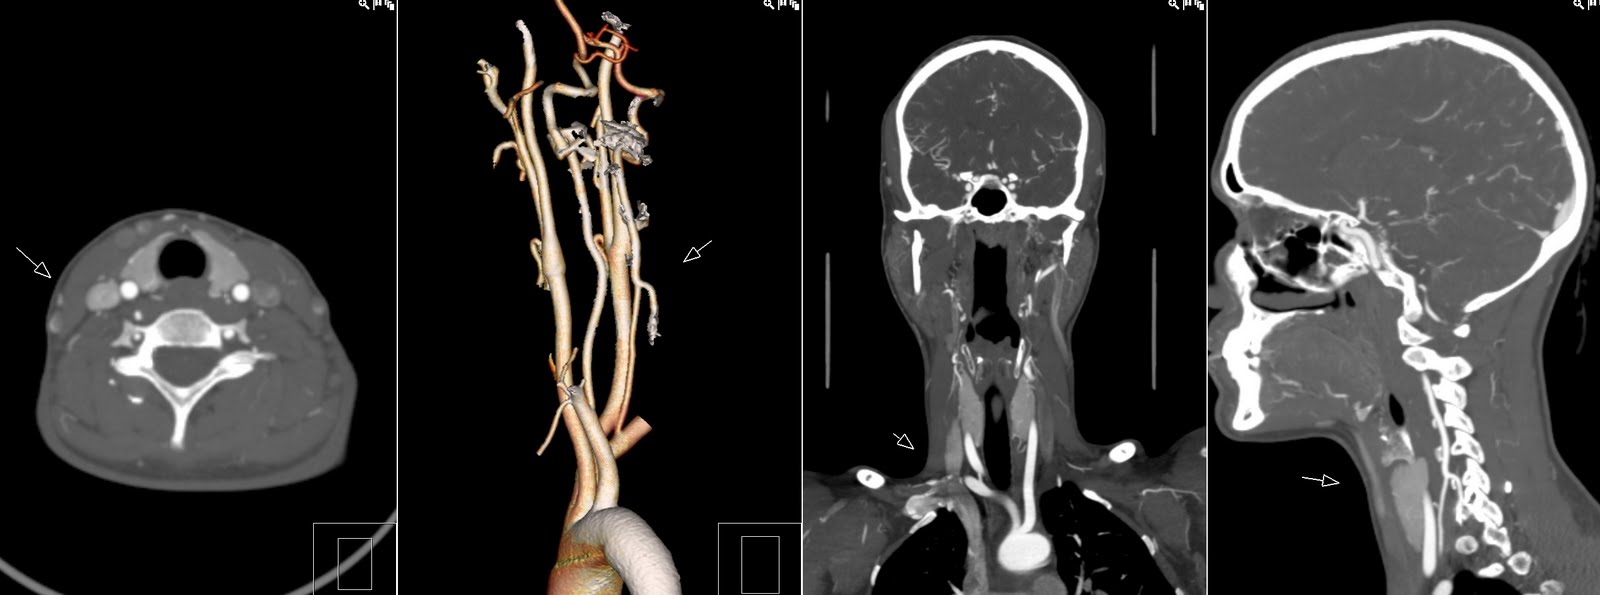

Аплазия мозгового

Аплазия мозгового 114 фотографий